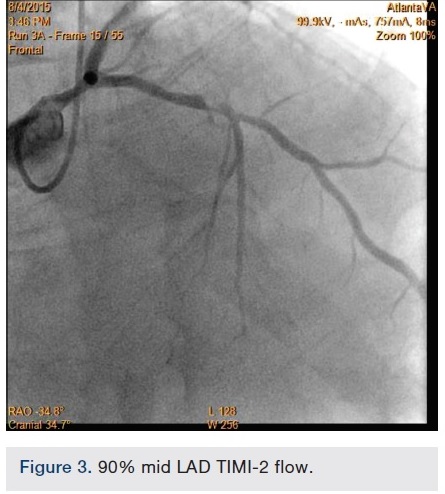

A 56-year-old man was on regular follow-up in our congestive heart failure (CHF) clinic for CHF with decreased ejection fraction. He gradually developed new Canadian Cardiovascular Society (CCS) III-IV anginal symptoms and had a cardiac catheterization revealing an angiographically significant, highly calcified proximal left anterior descending coronary artery (LAD) stenosis (90%) (Figure 1), intermediate left main (LM) disease (40-50%) (Figure 2), and complete occlusion of the distal right coronary artery (RCA) (Figure 3). Cardiac magnetic resonance imaging (MRI) revealed that the left ventricular apex and posterior walls might have limited viability.

Following successful completion of the peripheral phase, it was felt that a 4-week period was necessary for the iliac stent to heal somewhat (especially since we planned to place a 14 French Cook sheath through it). We then moved on to the coronary phase of this procedure. Bilateral groins and the right wrist were prepared and draped in the usual sterile fashion. Using micropuncture technique with fluoroscopic verification of needle entry into the left CFA at the upper quadrant of the femoral head, a 6 French sheath was placed in the left CFA. The existing left femoral arterial sheath was removed, and the arteriotomy was pre-closed with a single Perclose device (Abbott Vascular). The arteriotomy was then serially dilated with 10, 12 and 14 French dilators, and a 14 French, 30 cm Cook sheath was placed successfully in the left common femoral artery. Following therapeutic anticoagulation with intravenous heparin, a regular J-wire and a 6 French pigtail catheter were used to cross the aortic valve, and the catheter was used to exchange the J wire for the 0.018-inch Platinum Plus wire (Boston Scientific). The Impella CP (3.5) percutaneous left ventricular assist device (LVAD) (Abiomed) was inserted into the left ventricle over the Platinum Plus wire (Figure 8). The Impella was then activated and good flows were verified. Right radial artery access was obtained and a PB 3.0 7.5 French sheathless guide system (Asahi Intecc) was used to engage the left main coronary artery. The LAD was wired uneventfully using a Runthrough wire (Terumo) via a 1.25 x 6 mm over-the-wire (OTW) Sprinter balloon (Medtronic). This was then exchanged for a Viper wire (CSI). Orbital atherectomy of the proximal LAD lesion was performed with excellent results (80,000 rpm x 4 passes, 120,000 rpm x 2 passes) (Figure 9). The LAD wire was then exchanged for a Runthrough wire and the left circumflex (LCX) was wired with a BMW wire. Following plaque modification with orbital atherectomy, predilation of LAD was performed with 3.0 x 20 mm Chocolate Balloon (QT Vascular Ltd) (15 atmospheres x 60 seconds and 15 atmospheres x 30 seconds) (Figure 10) with an excellent result and no dissection (Figure 11). A 3.5 x 38 mm Promus stent (Boston Scientific) (14 atmospheres x 30 seconds) was placed from the left main into the proximal LAD lesion ensuring adequate coverage. The jailed LCX wire was recovered and re-placed in the LCX through the struts of the newly placed LM-LAD stent (Figure 12). Predilation of the LCX ostium was performed with a 2.5 x 8 mm Glider balloon (QT Vascular Ltd) (14 atmospheres x 25 seconds). The mid LAD was stented (ensuring overlap with proximal stent) with 3.0 x 16 mm Promus stent (16 atmospheres x 25 seconds). A final kissing balloon inflation of the LAD/LCX with an NC Sprinter 2.5 x15 mm balloon (Medtronic) into the LCX and a NC Sprinter 3.5 x12 mm balloon into the LAD was performed, with up to 16 atmospheres x 20 seconds on both (Figure 13). Final IVUS of the LM and LAD stent revealed excellent results and the LCX ostium looked excellent as well (Figures 14-16).